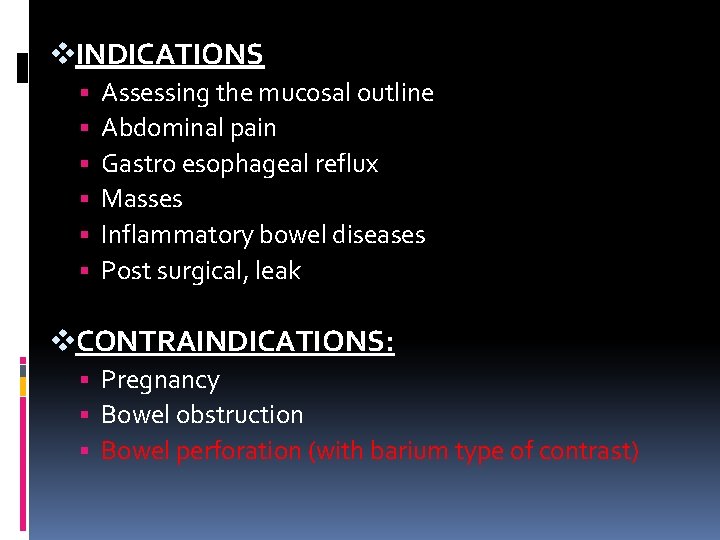

v. INDICATIONS Assessing the mucosal outline Abdominal pain Gastro esophageal reflux Masses Inflammatory bowel diseases Post surgical, leak v. CONTRAINDICATIONS: Pregnancy Bowel obstruction Bowel perforation (with barium type of contrast)